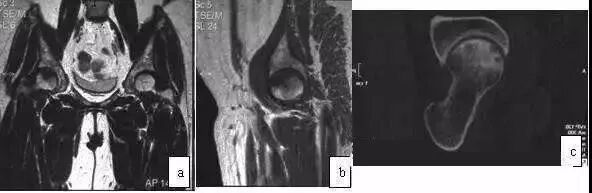

MRI的T1WI为弥散低信号,T2WI为高信号,范围累及整个股骨头、颈,甚至扩展至大转子(图4)。与ONFH不同的是ITOH无低信号带和双线征。X线片显示转子部骨量减少,因此鉴别不难。ITOH为自限性疾病,经非手术治疗4月~1年可完全恢复,包括MRI图像。

图4 女,45岁,突发性左髋疼痛,无诱因,诊断为暂时性骨质疏松症。(a)T2WI示股骨头颈及转子间弥散性高信号(冠状位);(b)T2WI示股骨头高信号(轴位);(c)T1WI示股骨头低信号;(d)X线片示股骨头颈及转子部骨量减少